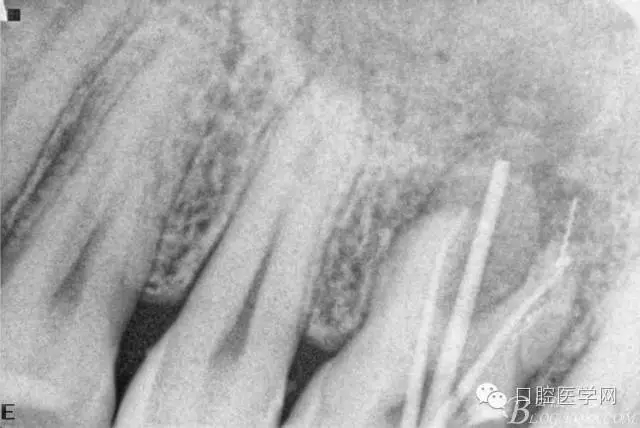

根充后三個月。

根充后四個月。根尖炎性陰影明顯減小,唯獨遺憾的是遠頰根一斷針,不知后續(xù)如何,日后再行根尖手術(shù)吧。